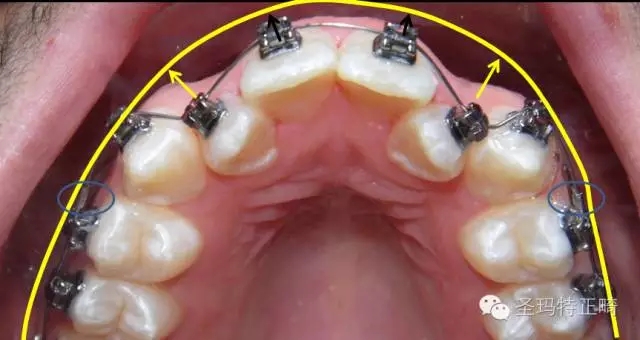

如圖所示,把阻擋管置于兩個(gè)1之間:上口放兩個(gè)阻擋管在1的近中端,如果兩個(gè)1不齊的話可放在其中一個(gè)1的近遠(yuǎn)中各一個(gè);下口可采用類似操作, 但由于空間限制,通常只放一個(gè)阻擋管,居中放置夾緊即可。

如圖所示,先將支抗牙的牙絲入槽,把阻擋管置于支抗牙的近中端,并使牙絲位于前牙托槽外側(cè)約1~2毫米處,夾扁固定阻擋管。按照正常操作步驟,完成牙絲入槽,即可在阻擋管的幫助下開始更為有效的擴(kuò)弓。